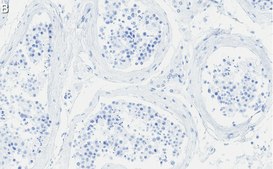

Immunohistochemistry (Paraffin) Analysis: A 1:100 dilution from a representative lot detected Anillin in human testis tissue sections.